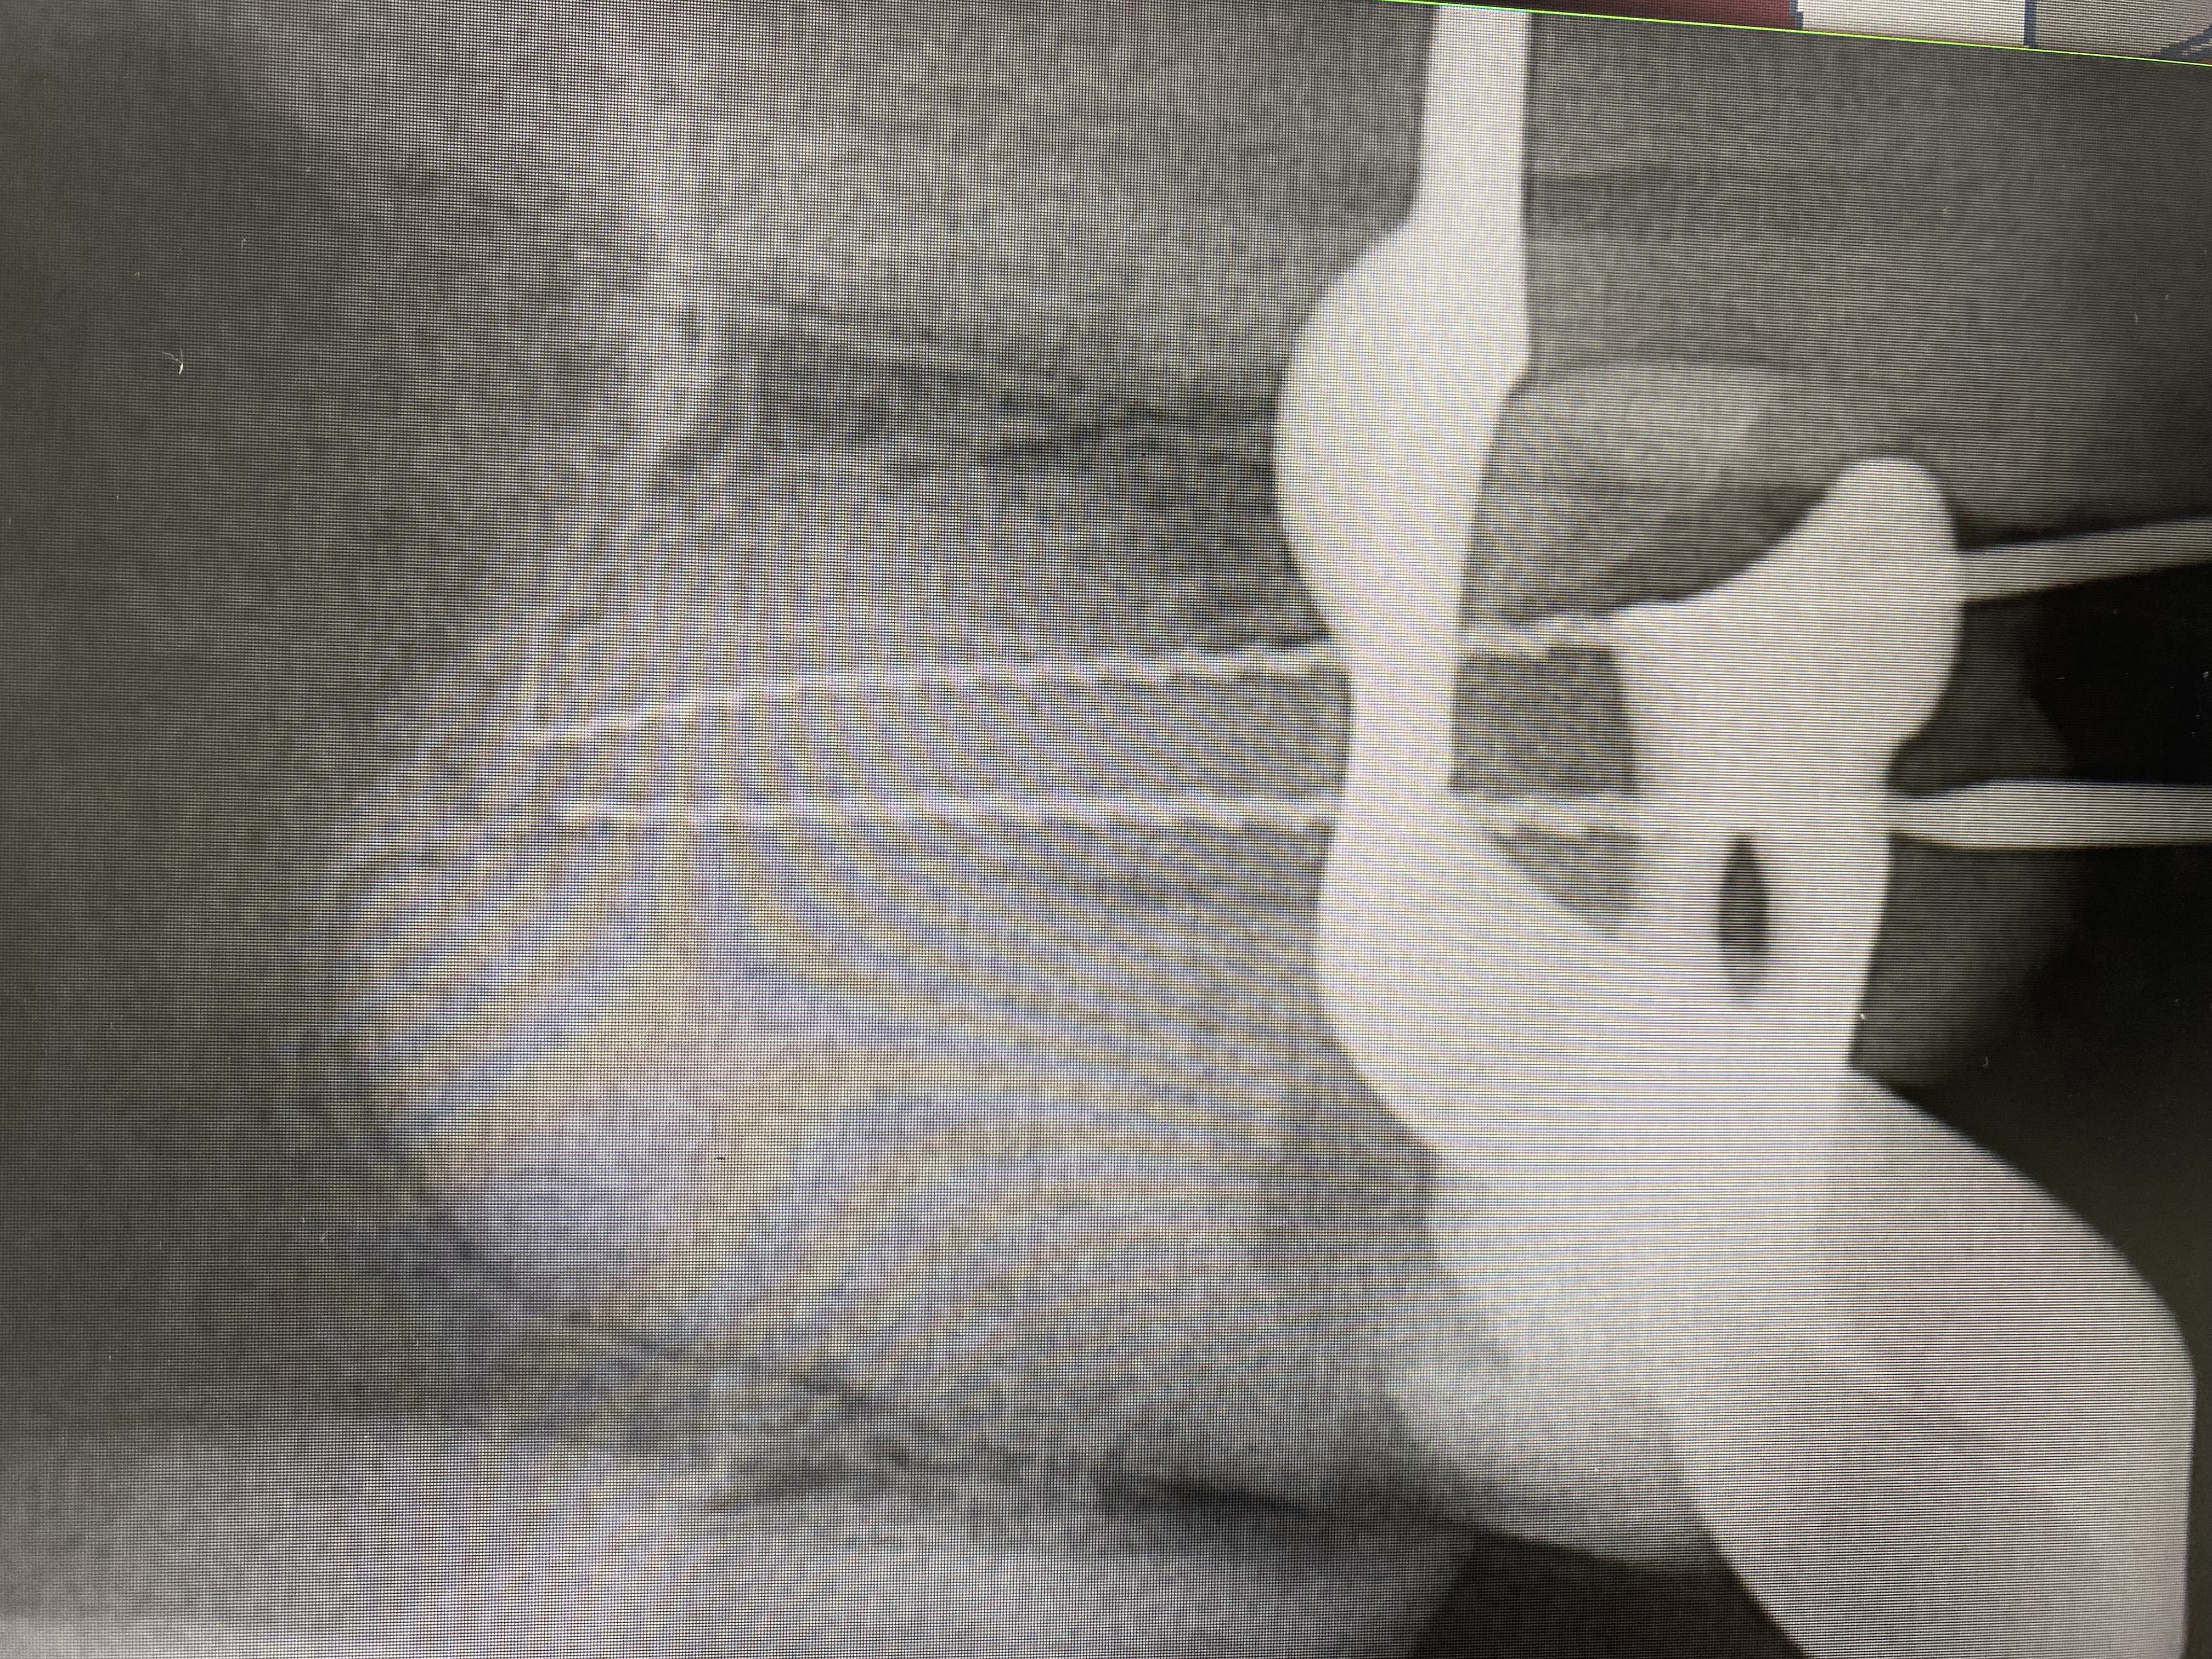

- Проведение полной профессиональной консультации по здоровью зубочелюстной системы, составление комплексного плана лечения, рекомендации по поддержанию качественной гигиены полости рта, обучение правильной технике чистки зубов, анализ снимков на визиографе и рентген-аппарате, анализ Клкт снимков

- Владение современными методиками пломбирования корневых каналов, обработки и распломбировки многокорневых зубов любой степени сложности